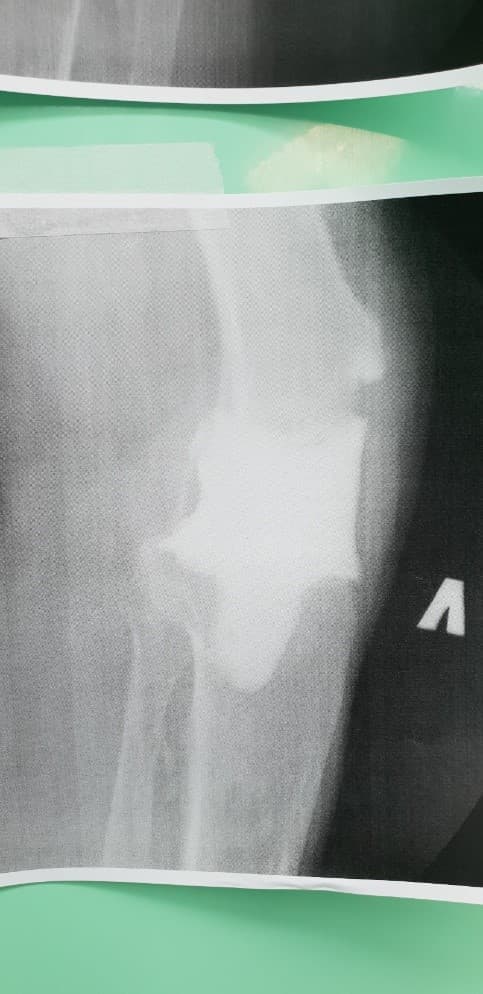

Үе дайрсан ясны анхдагч хавдар, ясны дутмагшлын үед хийгдэх мэс засалimg17Үе дайрсан ясны анхдагч хавдар, ясны дутмагшлын үед хийгдэх мэс засалimg18

Зураг 1. Сэргээн засах мэс заслын өмнөх рентген зураг. Эгц урд, хажуугаас авсан байдал.